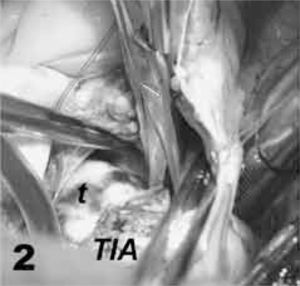

La pared del techo de la aurícula izquierda, a unos 2cm de la cara posterior de la aorta, se secciona con bisturí hasta alcanzar su luz, visualizándose la porción más superior del mixoma. Esta incisión es prolongada a tijera, por un lado, hacia la vena pulmonar superior izquierda y, por el otro, hasta el septo interauricular superior. A continuación se secciona la aurícula derecha en la base de la orejuela, a cierta distancia del nodo sinusal, y se prosigue la incisión hacia arriba y hacia el septo hasta conectar con la incisión auricular izquierda. Varios puntos de exposición se colocan en la parte anterior y posterior de la línea de incisión, y un aspirador flexible es deslizado suavemente al interior de la aurícula izquierda (Fig. 1).

Se inicia la sección con tijera de todo el espesor del septo interauricular donde se unen los techos de ambas aurículas, entre la vena cava superior y aorta ascendente, abarcando el área donde asienta la base de implantación tumoral, con un margen de seguridad peritumoral de 2–3mm. La pinza de disección sólo se utiliza para separar cuidadosamente el cuerpo tumoral de su base de implantación, pero nunca se presiona entre las ramas de la pinza el mixoma (Fig. 2).